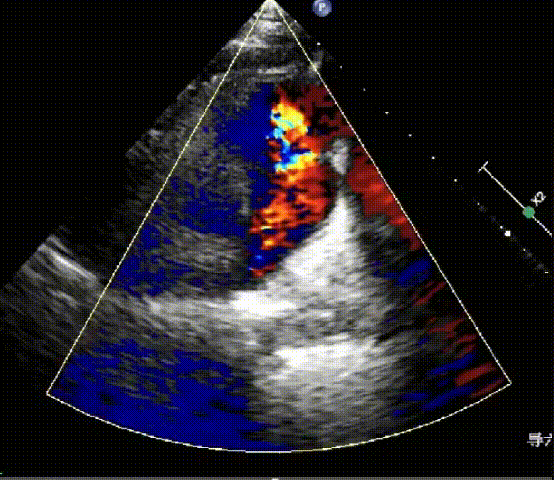

术前心脏超声

先天性心脏病,法洛氏四联症术后,重度肺动脉瓣关闭不全,最大跨瓣压差23mmHg,右室增大。

术后心脏超声

人工肺动脉瓣位置及功能正常,无明显关闭不全及瓣周漏。